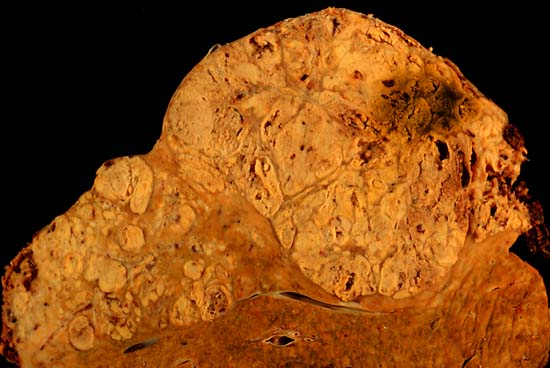

6. 1. 4. 간암

알코올은 간경화증을 통해 간암의 위험 요인으로 작용한다.[274][275][276] 간경화증은 주로 만성 알코올 사용으로 인해 간 내에서 흉터 형성으로 인해 발생한다.[277]

간경화증을 가진 사람 중 약 5%에서 간암이 발병한다. 간경화증은 알코올 남용으로 인한 손상 후 간 세포가 흉터 조직으로 대체되어 발전하는 질환이다.[278]

국가 알코올 남용 및 중독 연구소(NIAAA)는 장기간에 걸친 과도한 음주가 지속된 경우 원발성 간암과 관련되었다고 보고하였다. 그러나 알코올 또는 다른 요인으로 인한 간경화증이 암을 유발시키는 주된 원인으로 여겨진다.[279][280]

미국 국립암연구소(NCI)는 하루에 다섯 번 이상의 음료를 섭취하는 경우 간암 발병 확률이 현저히 증가한다고 보고하였다.[245]

연구에 따르면 매일 정기적으로 추가로 소비하는 음주 한 잔당 간암 발생률이 1000명당 0.7씩 증가한다.

미국에서 간암은 비교적 희귀한 편이며, 약 10만 명당 약 2명 정도에 영향을 미치지만, 이 케이스 들 중 최대 36%가 과도한 알코올 소비와 관련이 있다고 일부 연구자들이 언급하고 있다.[281][282] 전체적으로 간세포암(HCC)의 61%는 C형 간염 바이러스(HCV)로 인한 것이며, 13%는 B형 간염 바이러스(HBV)로 인한 것이며, 18%는 과도한 알코올 소비로 인한 것이다.[283] 북부 이탈리아의 브레시아 지역에서 실시된 연구는 인구 기여위험도(AR)를 기준으로 볼 때, 과도한 알코올 섭취가 이 지역에서 간세포암(HCC)의 가장 주요한 원인으로 보이며(AR: 45%), 그 다음으로 HCV(AR: 36%) 및 HBV(AR: 22%) 감염이 있다고 하였다.[284]